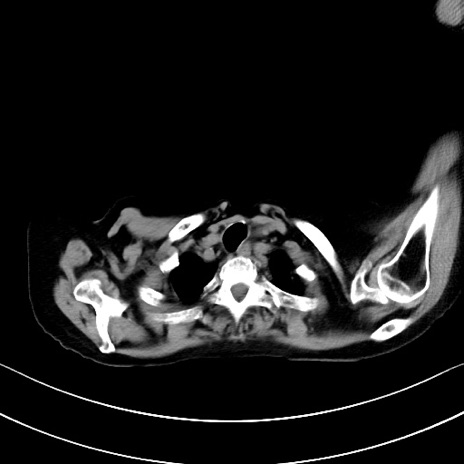

横断像

他院CT